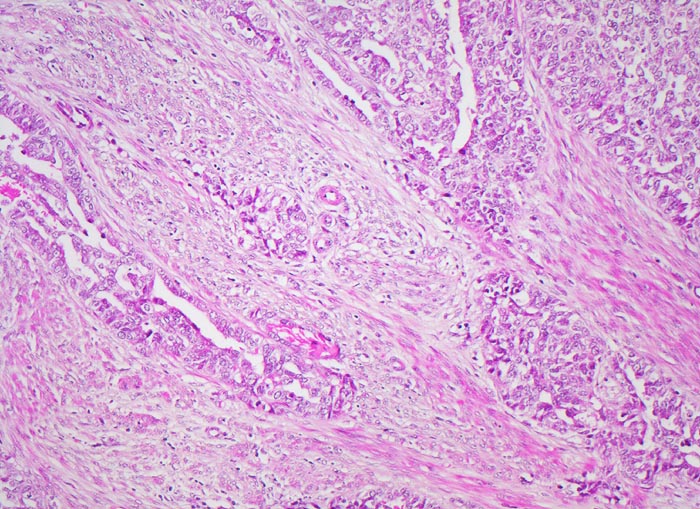

Endometrioide Karzinome bestehen aus tubulären Drüsen, welche von einem mehrreihigen Epithel ausgekleidet werden. Schleim ist meist nicht oder nur apikal in den Zellen vorhanden. Die Ausdehnung der soliden Areale und die zytologischen Atypien bestimmen den Differenzierungsgrad (low-grade versus high-grade). Metaplastisches Plattenepithel findet sich häufig in endometrioiden Karzinomen und hilft bei der Abgrenzung von anderen Subtypen. Das endometrioide Karzinom kann sich innerhalb von Adenomyoseherden im Myometrium entwickeln (> 4482). In diesen Fällen kann die Bestimmung der Infiltrationstiefe erschwert sein.

• Endomyometranes Gewebsfragment.

• Die rechte Seite des Uteruskavums wird ausgekleidet von flachem atrophem Endometrium. Im Cavum liegt ein Blutkoagel mit nekrotischem Detritus nach vorausgegangener diagnostischer Utersukurettage.

• Anstelle des Endometriums findet sich in der linken Hälfte des Uteruskavums ein Adenokarzinom bestehend aus architektonisch komplexen Drüsen. Die Drüsen liegen teils dos à dos ohne erkennbares Stroma zwischen zwei Drüsenschläuchen.

• Tumorzellverbände infiltrieren die glatte Muskulatur des Myometriums.

• Tumordrüsen ausgekleidet von mehrreihig angeordneten Tumorzellen mit hyperchromatischen polymorphen längsovalen Tumorzellkernen mit zahlreichen Mitosen. Die Morphologie der Tumordrüsen erinnert an proliferatives Endometrium.

• Anmerkung: Typischerweise ist das endometrioide Karzinom des Uterus als Folge des ursächlichen Hyperöstrogenismus assoziiert mit einem hyperplastischen Endometrium (siehe Präparat 148). Im Kurspräparat erscheint hingegen das nicht-neoplastische Endometrium nach vorausgegangener Kurettage atroph. Atrophes Endometrium findet sich sonst charakteristischerweise neben serösen Endometriumkarzinomen postmenopausaler Patientinnen. Das sollte der Kliniker dem Pathologen mitteilen: